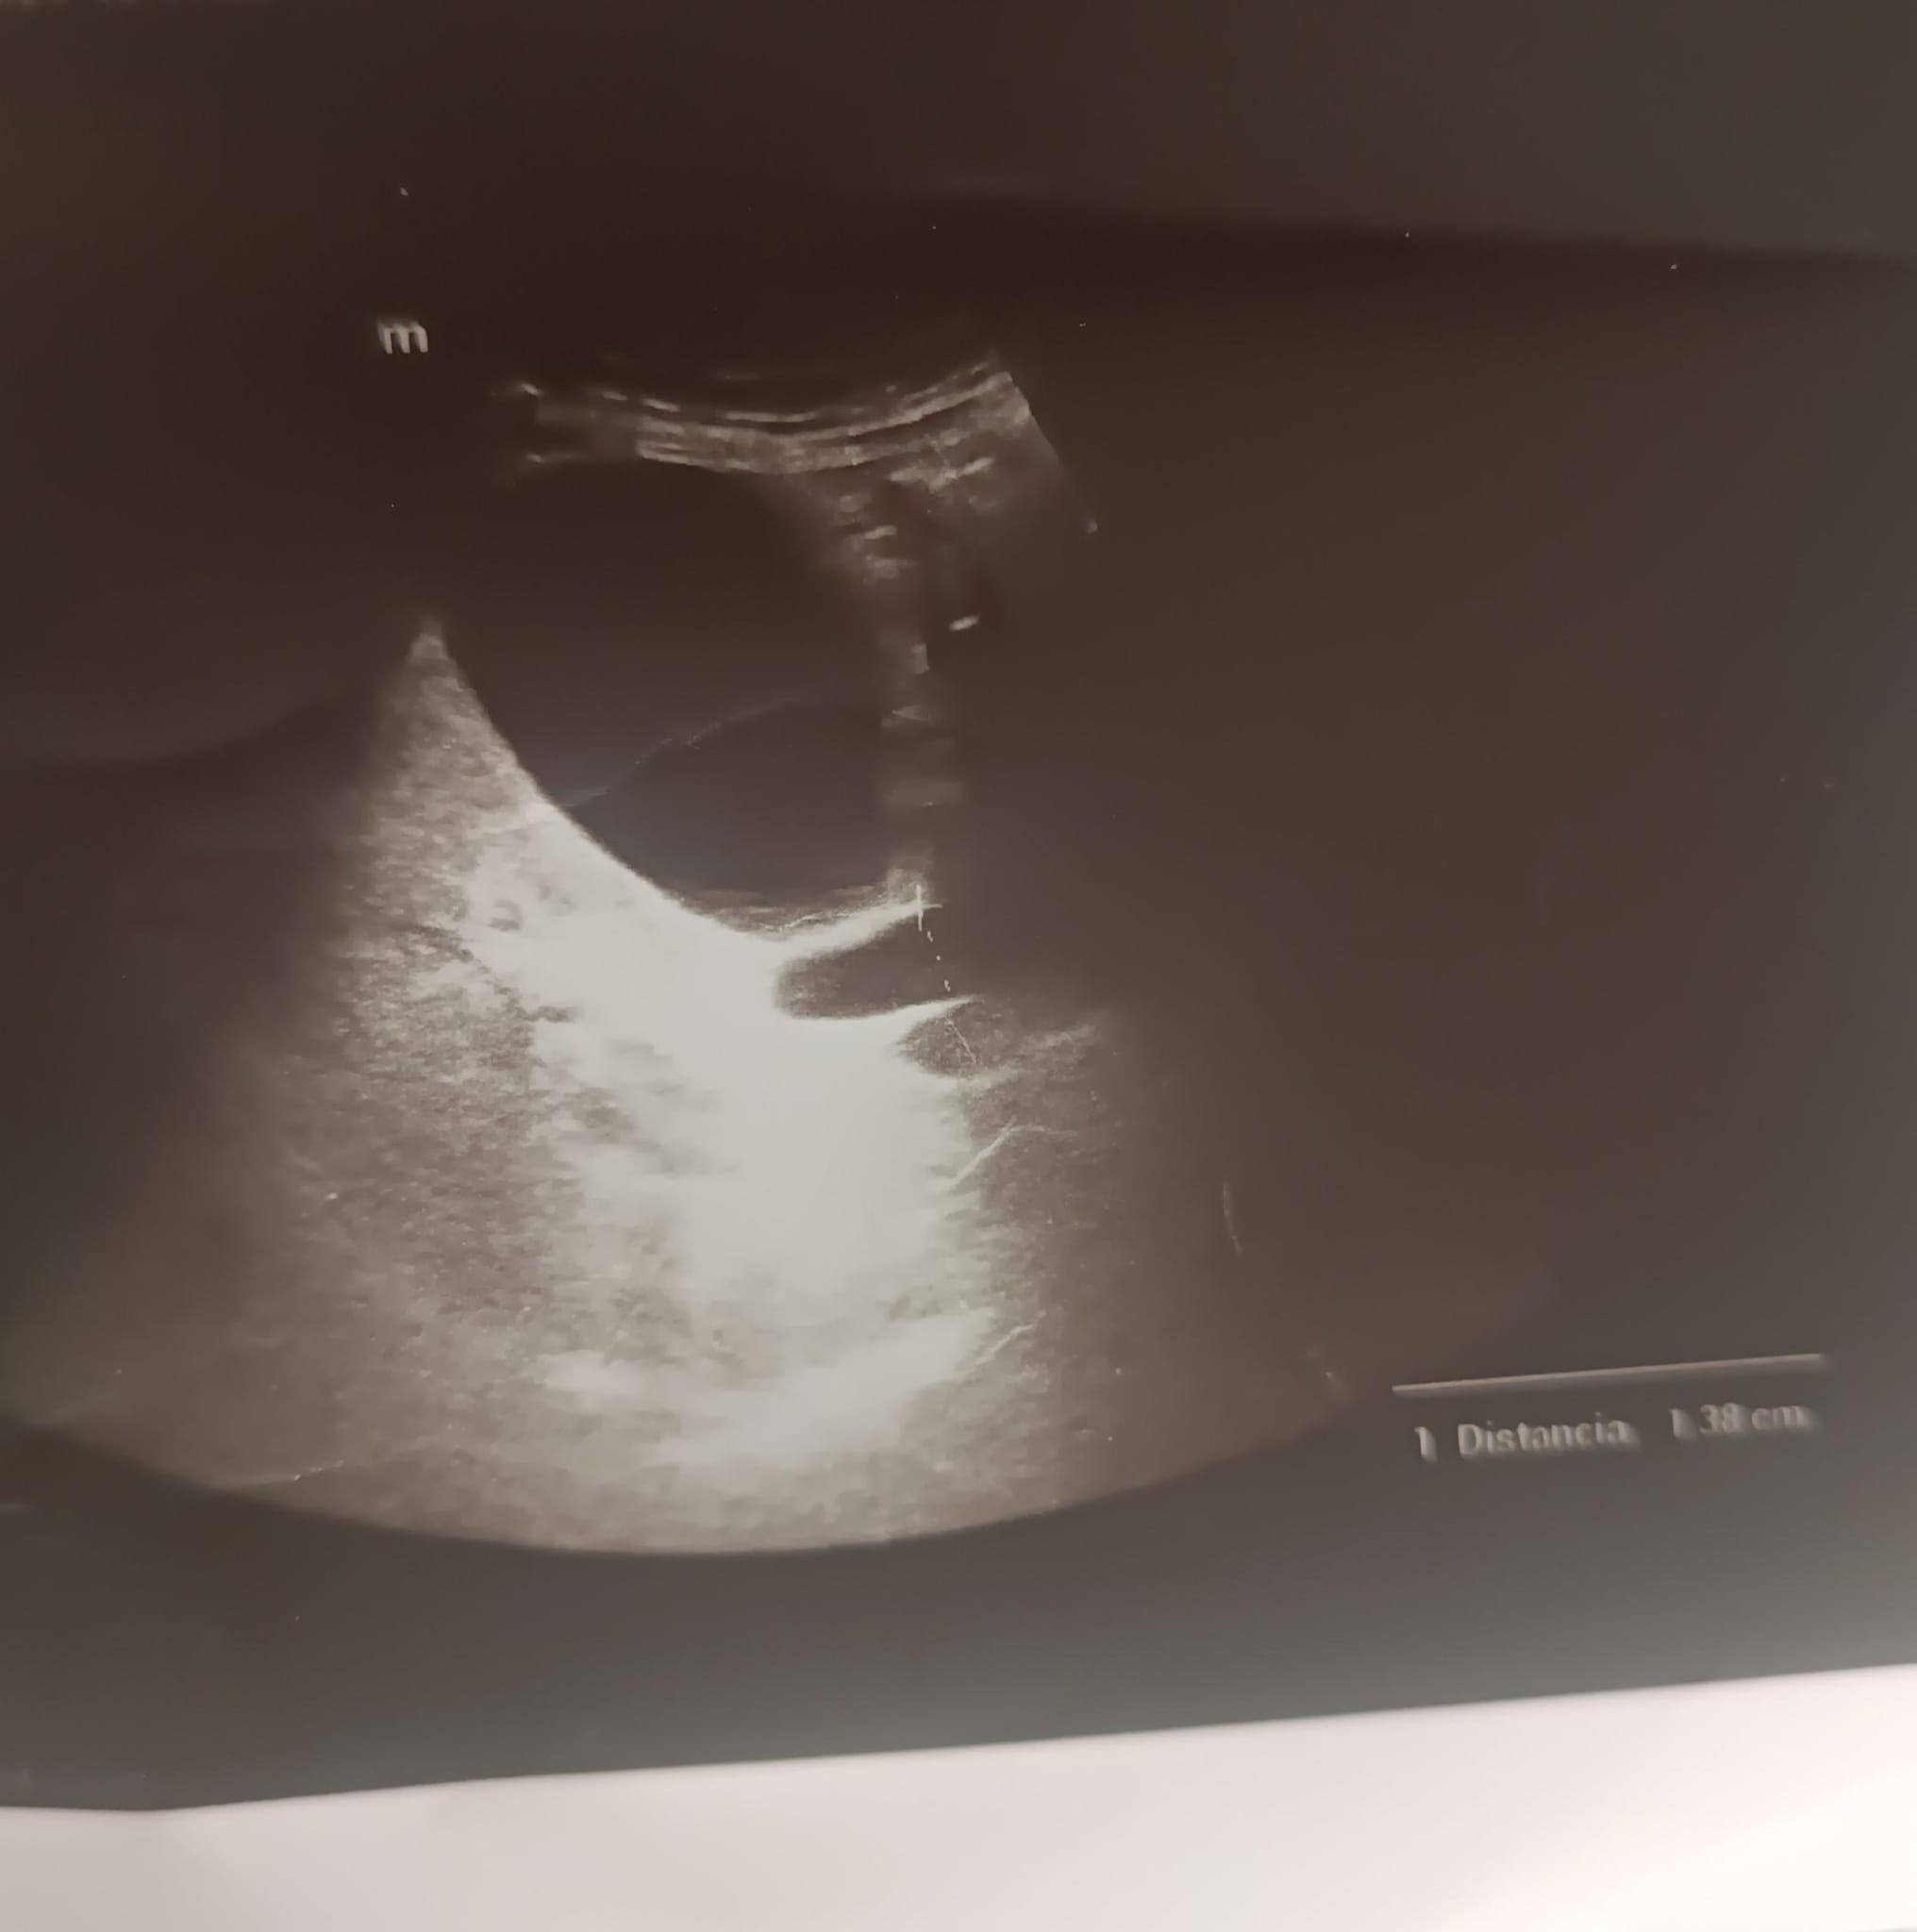

Murphy ecográfico positivo. Imagen de doble cañón, colédoco de 1.3cm, vesícula moderadamente distendida: vía biliar extrahepática dilatada. Datos de esteatosis hepática moderada/severa. Ante estos hallazgos que se decidió por derivación a urgencias hospitalarias en vez de una derivación a consulta de alta resolución.